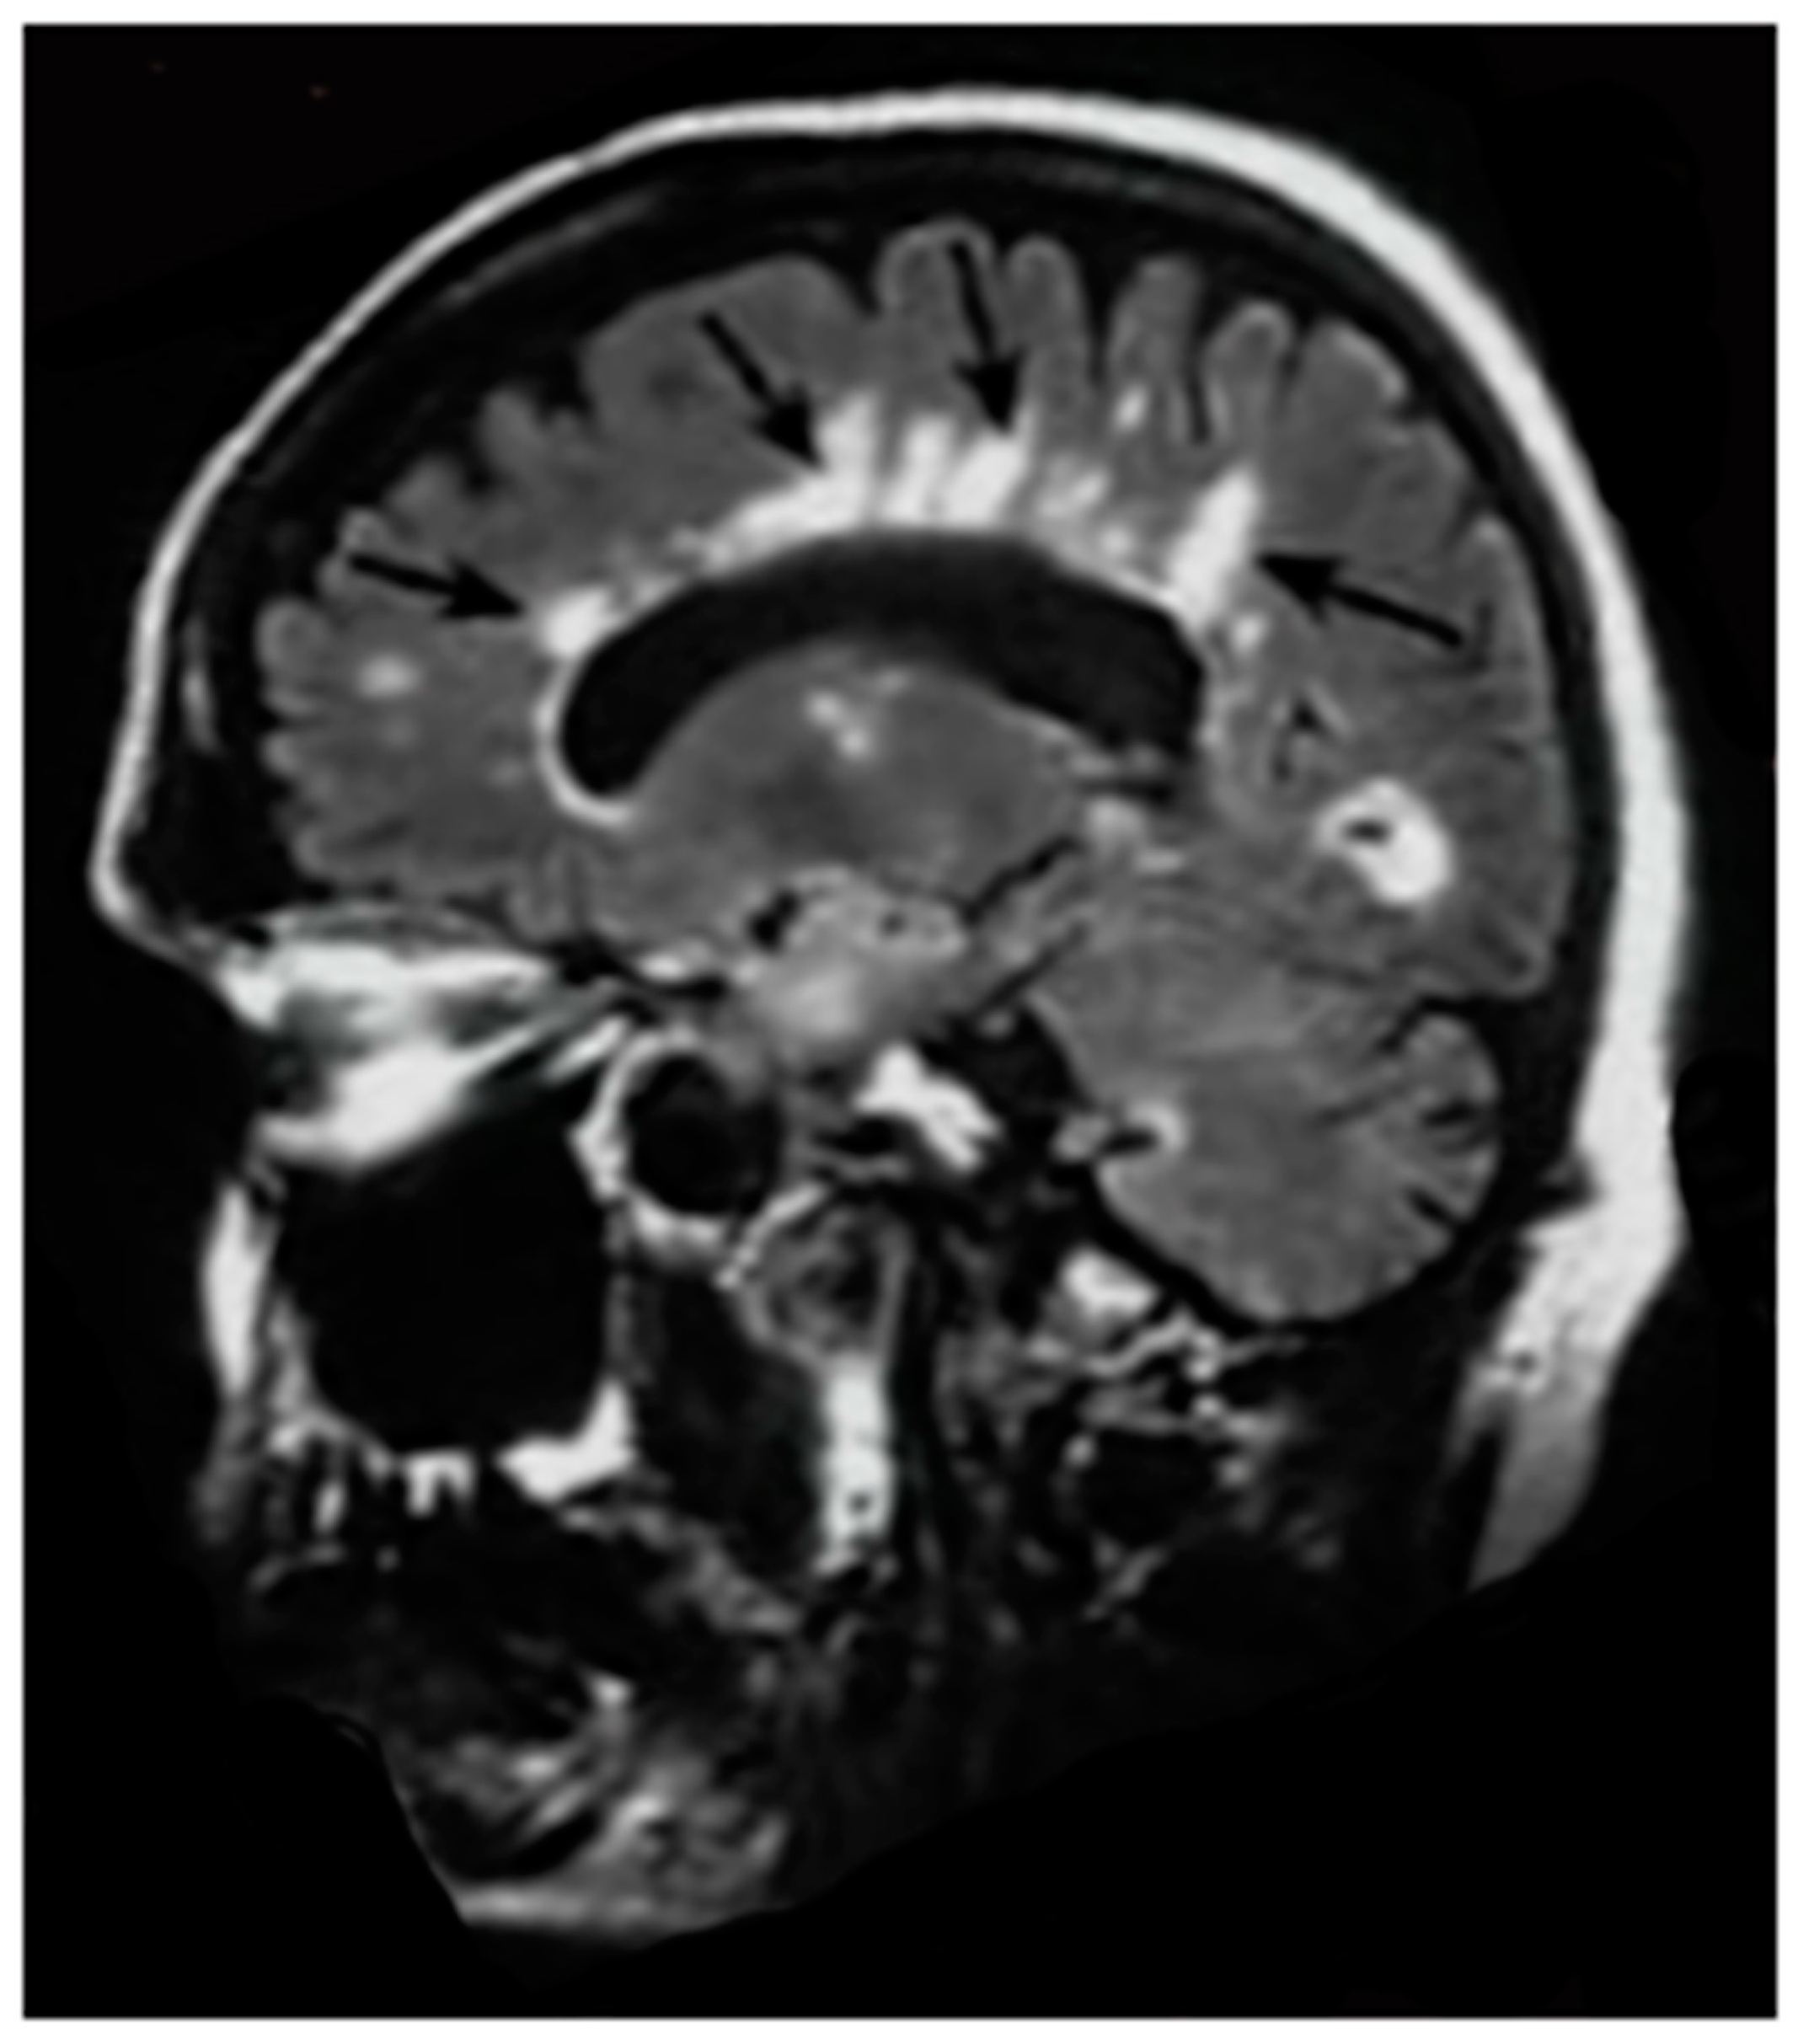

Figure 7.

Multiple sclerosis (MS): CT (left) and inversion recovery (IR) (right) (November 1981) [7]. Two larger lesions are seen on the CT image (left, arrows). These are also seen on the IR image (right, arrows). There are an additional six lesions seen in the periventricular white matter on the IR image (arrows). The additional lesions are seen in normal appearing white matter on the CT image.